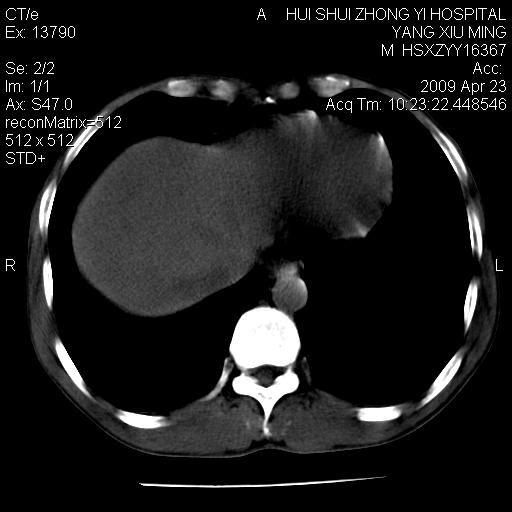

上腹部疼痛一月,呕吐10天,发现左侧颈部包快10天 胸部cr片未见明显异常。

腹膜后淋巴结增大,转移、淋巴瘤?胰腺增大,胰腺炎?占位?颈部考虑增大淋巴结。建议腹部增强扫描。

黑!广泛淋巴结肿大不符合胰腺癌转移。胰腺周围淋巴结肿大致使胰腺看起来大。考虑淋巴瘤可能大。